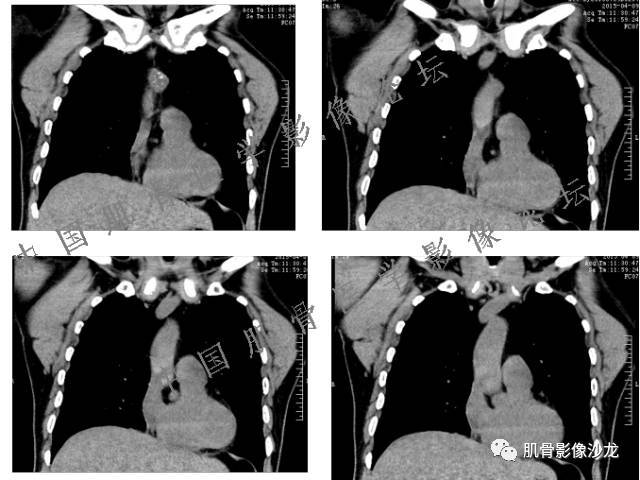

雪舞 :第二例,位于骶骨,有骨质破坏并有软组织肿块,软组织肿块边界清

向以四 : 病例2 感染性骶髂关节炎 TB可能大,左侧梨状肌受累、肿胀增粗,并见低密度脓肿?

西门吹雪:考虑恶性肿瘤 的确有些难

晴朗 :倾向肉瘤

医影在线 : 转移瘤要除外

致远 : 或者软骨肉瘤

张小林:炎性病变和肿瘤的鉴别

飞鹰行动 :有一定的骨质硬化,骨肉瘤及软骨肉瘤可能性大 晴朗: 有骨膜反应,有软组织肿块

雪舞: 第二例我们能够看到破坏与软组织肿块不成比例,软组织肿块大,破坏小

医影在线: 病变无明显钙化

雪舞 :第二例挺难的,骨质破坏是溶骨性的,局部皮质中断,软组织肿块外缘光滑

医影在线 :无软骨钙化

飞鹰行动 :有的软骨肉瘤可以没有钙化

晴朗 :软骨基质不一定都是钙化的

雪舞 : 软骨肉瘤的发病率居原发性恶性骨肿瘤的第三位,其特点是肿瘤内具有软骨基质

雪舞:弓形钙化,钙化比例少于面积的1/3,钙化边缘模糊

雪舞 : 都是软骨肉瘤鉴别于内生软骨瘤有意义的区别点